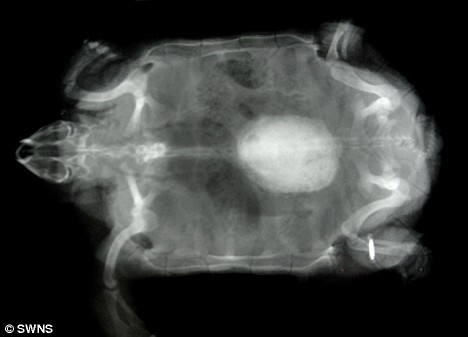

X光顯示波莉體內(nèi)的結(jié)石

獸醫(yī)組負責人莎倫·雷德羅塞介紹說,獸醫(yī)日前為園內(nèi)的動物做了例行體檢,當用X光照一只名叫波莉的雌性非洲餅干龜時,醫(yī)生們驚奇地發(fā)現(xiàn)它體內(nèi)竟然有一個雞蛋大小的東西,而5歲大的波莉身長才不過5.5英寸(約合14厘米)!

雷德羅塞表示,如果不取出波莉體內(nèi)碩大的結(jié)石,它最終將因腎衰竭而死去。給龜實施麻醉非常具有挑戰(zhàn)性,必須受過專門訓練的獸醫(yī)才能進行,但是鑒于波莉已經(jīng)出現(xiàn)不適,動物園的獸醫(yī)還是決定盡快去除它體內(nèi)的結(jié)石。手術(shù)共進行了一個小時,獸醫(yī)先是在波莉腹部的殼上切開一個洞,然后取出結(jié)石,最后再把切開的殼粘合起來。取出的結(jié)石重19克,大小為1.5英寸×1.2英寸(約合4厘米×3厘米)。據(jù)分析,這塊結(jié)石是波莉體內(nèi)的鈣沉積形成的。